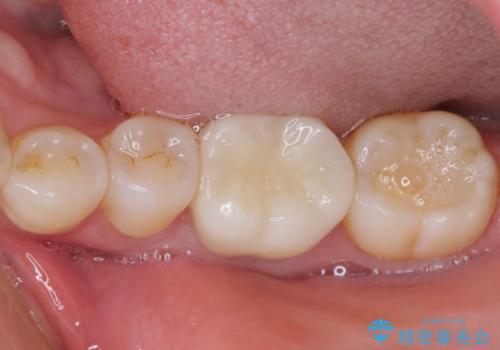

処置後、下顎の膿の出口はすぐに消えましたが、レントゲン写真からも分かるとおり、歯根途中に穴が開いており、充填材が歯根外にはみ出していました。数ヶ月経過を見たところ、特に異常は認められなかったため、補綴治療を行いました。